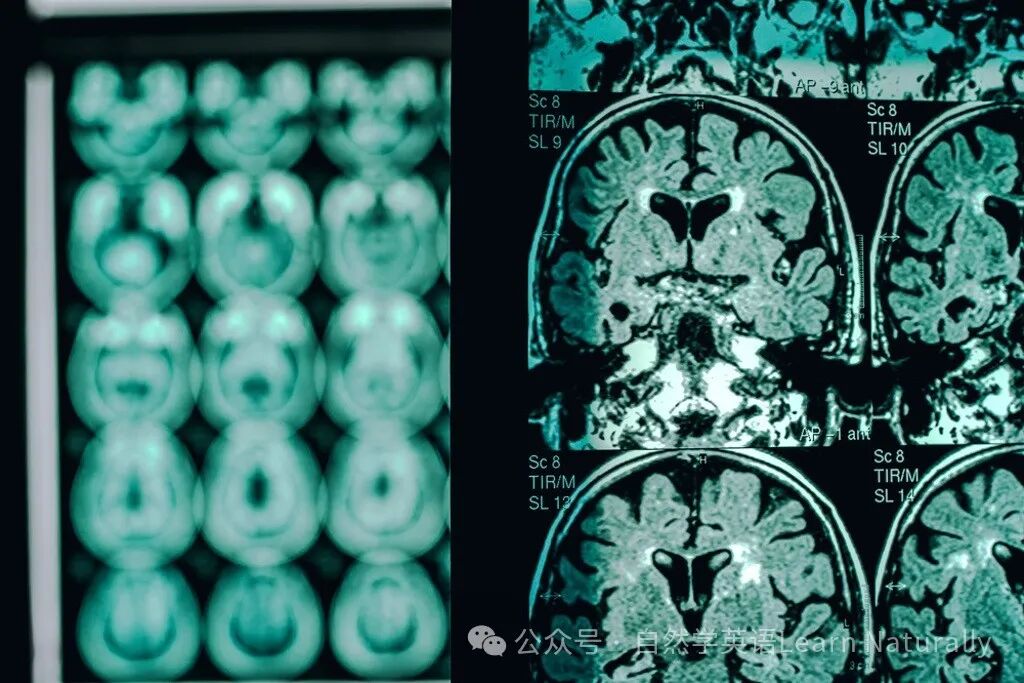

The study, published Monday in the journal Nature Medicine, provides the first reported evidence of medically acquired Alzheimer’s disease in living people. In these cases, the patients’ early-onset dementia symptoms may be the result of the possible transmission of amyloid beta protein, which is a key component of Alzheimer’s disease when it forms plaques in the brain.

这5名成人患者幼年时期因缺乏生长激素,于1959至1985年间从死者身上接收脑下垂体生长激素,不过后续相继出现阿兹海默症症状,当中3名患者的大脑扫描结果与诊断一致,2名患者验出符合阿兹海默症的生物标记,其中最年轻的患者仅38岁。